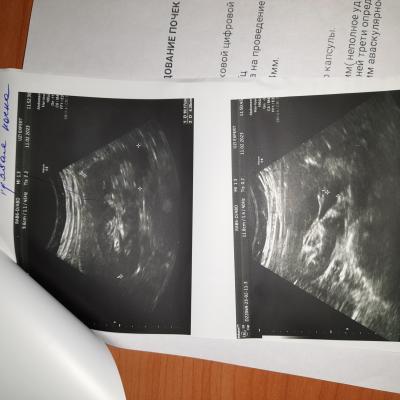

УЗИ почек, образование

Можно консультацию по УЗИ почек.

На сколько это серьёзно и опасно.

Добрый день! Для уточнения диагноза надо выполнить КТ почек с контрастированием. Далее - по ситуации. Удачи.